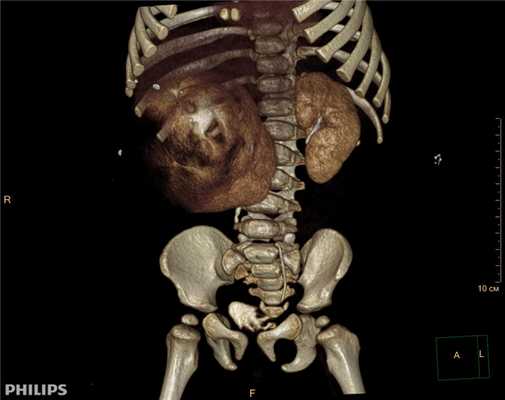

3D-реконструкции опухоли Вильмса пациентов детского отделения НМИЦ онкологии им. Н.Н. Петрова

Опухоль Вильмса. Компьютерная томография